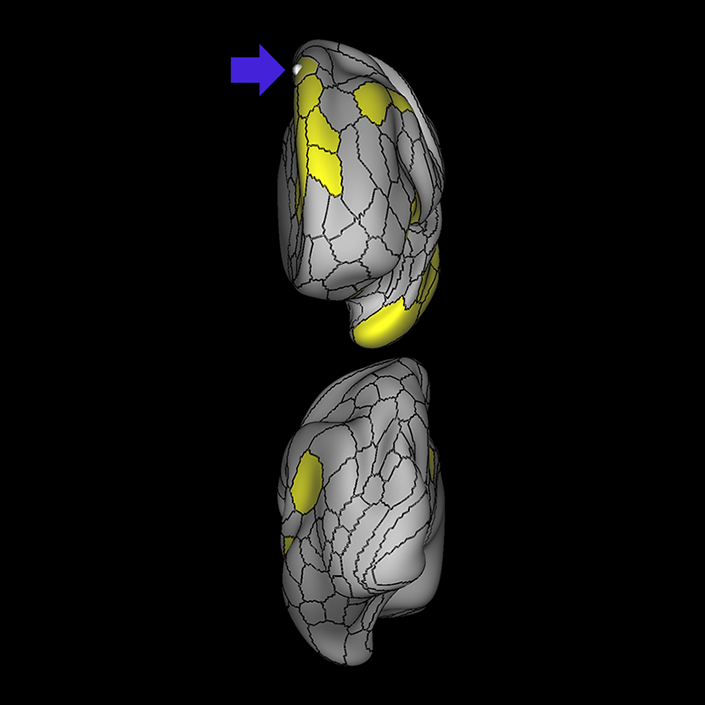

ᐅ SummaryArea 44: part of the inferior frontal gyrus of the lateral frontal lobe. Translates abstract and intentional information in the prefrontal cortex to more detailed representations to help guide the production of verbal and manual actions. In addition to its known association with Broca's area, is sometimes represented as part of Broca's complex ᐅ Where is it?Area 44 is at the posterior most part of the inferior frontal gyrus. It is the anterior bank of pars opercularis of the IFG. ᐅ What are its borders?Area 44 borders area 45 anteriorly and area 6r posteriorly. Area 8C is its medial border and its inferior border is wedged between then upper borders of Areas 6R and 6V. Its superior edge borders IFSp and IFJa. Its opercular surface is FOP4. ᐅ What are its functional connections?Area 44 demonstrates functional connectivity to areas SFL, IFSp, IFJa, 45, 47s, 47L, 9a, 9m, 8AV, 8BL and 8C in the dorsolateral frontal lobe, area 8BM in the medial frontal lobe, area 55b in the premotor areas, areas FOP5, AVI and PSL in the insula- opercular region, areas TGd, STSdp and STSvp in the temporal lobe, areas PFm, and PGi in the inferior parietal lobe, and no areas in the medial parietal lobe. ᐅ What are its white matter connections?Area 44 is structurally connected to the arcuate/SLF and the FAT. Connections with the arcuate/SLF project posteriorly and wrap around the Sylvian fissure to the middle temporal gyrus to end at TE1a and TE1m. There are also projections from the arcuate/SLF before it terminates to parcellations A5 and STSdp. The majority of the inferior connections of the frontal aslant tract end at 44, the tract is connected superiorly to superior frontal gyrus parcellations SFL, 6ma and s6-8. Local short association bundles are connected with 45 and 8C. White matter tracts from 44 in the right hemisphere have less consistent connections with the arcuate/SLF. ᐅ What is known about its function?Area 44 translates abstract and intentional information in the prefrontal cortex to more detailed representations to help guide the production of verbal and manual actions. Area 44, in addition to its known association with Broca's area, is sometimes represented as part of "Broca's complex", including Brodmann Areas 45, 46, 47 and the mesial supplementary motor area of 6, which contribute to a frontal-subcortical circuit. The right pars opercularis has also been implicated in cognitive inhibition in the overall context of working memory. |

A: lateral-medial

B: anterior-posterior

C: superior-inferior

DTI image |